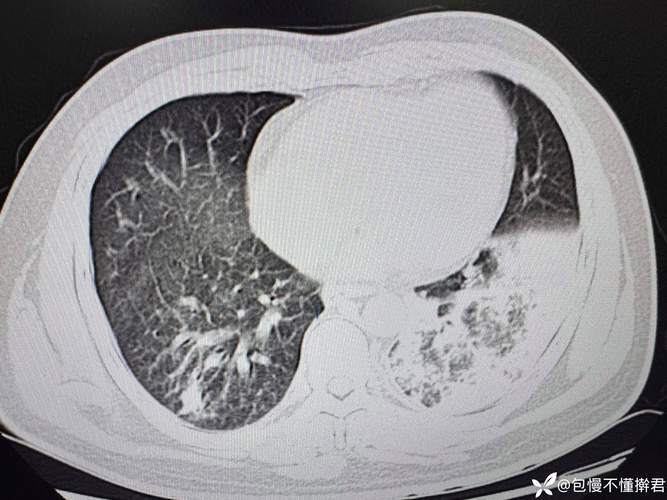

肺部感染 → 加重呼吸衰竭

- 感染加重肺损伤: 肺部感染(如肺炎)会导致肺泡内充满炎症渗出物(痰液、脓液),这使得肺无法有效地进行氧气和二氧化碳的交换。

- 通气/血流比例失调: 健康的肺部需要空气(通气)和血液(血流)完美匹配,感染区域有血流但没有足够的空气,而健康区域有空气但血流可能减少,这大大降低了呼吸效率。

- 结果: 身体缺氧(低氧血症)和二氧化碳潴留(高碳酸血症),从而加重或导致新的呼吸衰竭。

肺部感染的治疗(对症和对因治疗)

- 抗感染治疗:

- 经验性用药: 在痰液或分泌物培养结果出来之前,医生会根据经验使用广谱、强效的抗生素,覆盖可能的致病菌(如革兰氏阴性菌、金黄色葡萄球菌等)。

- 目标性用药: 一旦痰培养或血培养结果回报,会根据药敏试验结果,调整为最敏感、最精准的抗生素。

- 气道管理:

- 翻身拍背: 定时为患者翻身、拍背,利用体位引流帮助痰液松动。

- 吸痰: 对于使用呼吸机的患者,需要通过气管插管或气管切开导管,定时或按需吸出气道内的痰液,这是控制感染的关键。